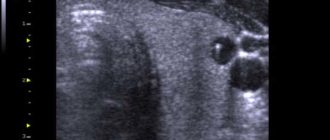

УЗИ показало узел на щитовидной железе

Узлы (узелки) щитовидной железы Паренхима (ткань) нормальной щитовидной железы имеет однородную структуру. Если во